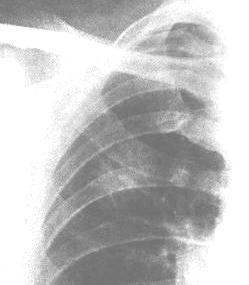

在无症状的病人,胸部X线常可见一个外周性小结节性肿块.如肿块直径<5~6mm,则难以发现.以往的X线检查结果对了解新生物颇有价值。对较小的孤立结节,穿透性强的X线和体层摄片可显示钙化,钙化的数量必须超过一个斑点,才能诊断为良性肿瘤或慢性肉芽肿性病变并排除肺癌。CT可显示其他技术看不到的病变,并可根据有无淋巴结扩散的迹象有助于肿瘤的分期。偶尔需要胸部磁共振成像(MRI)检查,对显示肺尖Pancoast瘤有无胸壁及椎体侵犯最有帮助。

有症状的病人,胸部X线可显示支气管狭窄和不规则肺实质浸润,或肺不张。在阻塞区或在周围型肿瘤内部可能看到空洞形成。阻塞性肺气肿不常见。偶尔,X线可显示在不相邻的肺叶内有浸润或阻塞区,此种现象不能用单个肿瘤灶解释而是支气管树弥漫性粘膜下淋巴渗透的结果.胸膜渗液往往与浸润性或外周部肿瘤有关,胸液的细胞学检查或胸膜活检可提供诊断。极少数情况下,在尚未发现肺内病灶时,痰中即可找到肿瘤细胞。